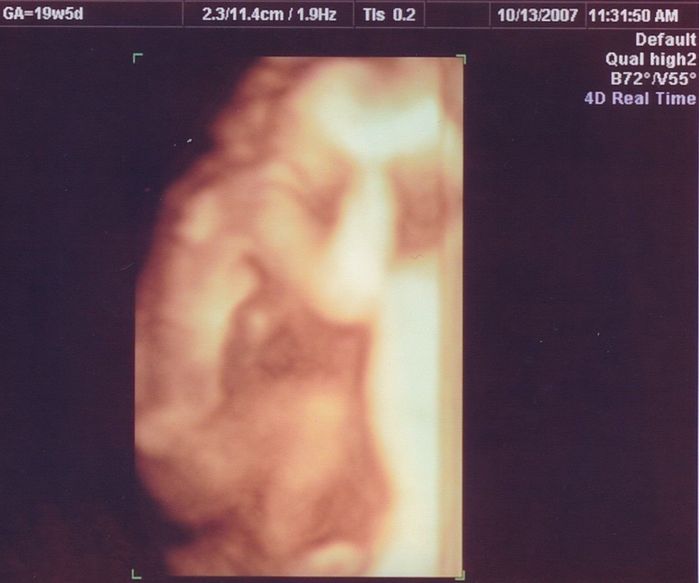

妊娠19週目のエコー写真

安定期に入り、検診のたびに体重や血圧を測るようになりました。前回の検診時から、8~10kgの増加が目安と言われていましたが、妊娠15週から19週の間ですでに1.3kg増。強い食欲と眠気に勝てない毎日に危機感が募り、マタニティーヨガ、マタニティービクスを開始しました。